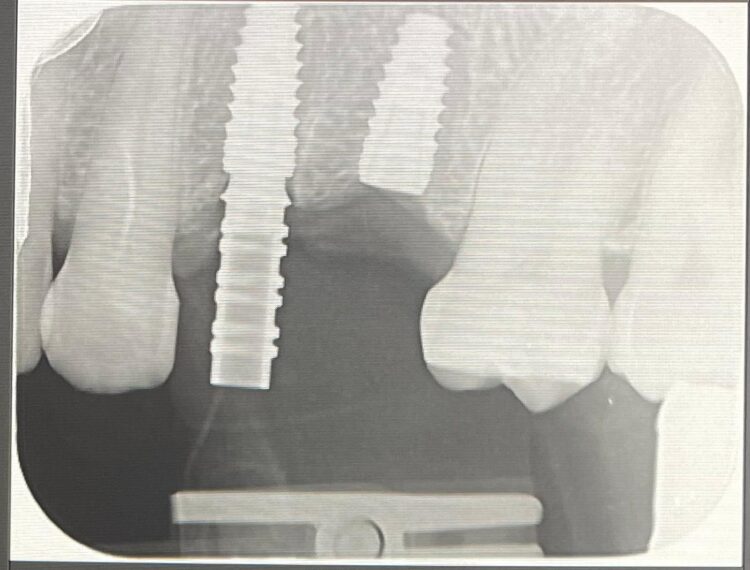

Two 3.8mm diameter CONELOG® Progressive-Line implants were placed through the guide, following the plan precisely. The UL4 implant was longer (11mm) to ensure sufficient apical bone was engaged for primary stability, it was also positioned in the palatal root to ensure good engagement with the bone and better bone to implant contact. A sizable jump gap was noted between the implant and the buccal plate of around 5-6mm. From a biological perspective, the jump gap can be left because the ridge would heal to leave a sufficient buccal plate. However, the literature[iv] shows that grafting reduces the amount of bone resorption post implant placement, which was one of the reasons that augmentation was indicated in this case.

An x-ray was taken immediately post-operatively to confirm that the temporary cylinder was seated correctly and wasn’t catching on the socket walls. This image also provided a reference for the custom healing abutment position and ensured that the bone graft material added to the jump gaps wasn’t preventing this abutment from fully seating.